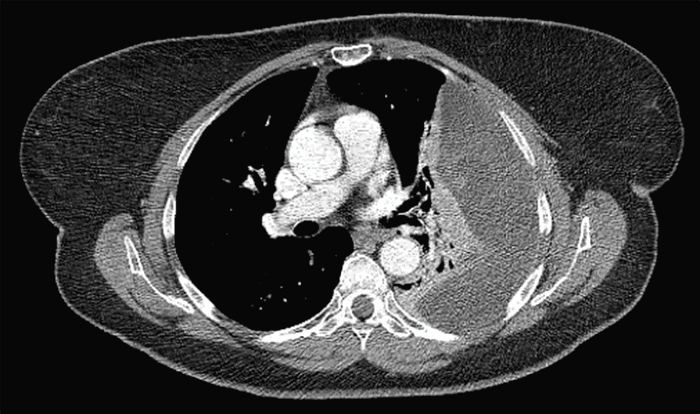

A 68-year-old female presented to our institution with abdominal pain, shortness of breath, and right-sided chest pain. A chest radiograph, obtained as part of a routine wellness visit, incidentally revealed a left-sided pleural effusion and ipsilateral atelectasis (Figure 1). At that time, the patient was asymptomatic, without shortness of breath, chest pain, cough, fever, or weight loss. A CT scan of the chest demonstrated a large, heterogeneous pleural effusion with internal septations, suggestive of loculation, and no evidence of masses or nodules within the lung parenchyma (Figure 2). The patient subsequently underwent ultrasound-guided thoracentesis, yielding only 30 mL of pleural fluid, which was sent for cytology, cell counts, cultures, and chemistry analysis. Pleural fluid analysis returned negative for malignancy, with benign mesothelial cells and chronic inflammatory cells.

Figure 1. Preoperative Chest Radiograph. Published with Permission